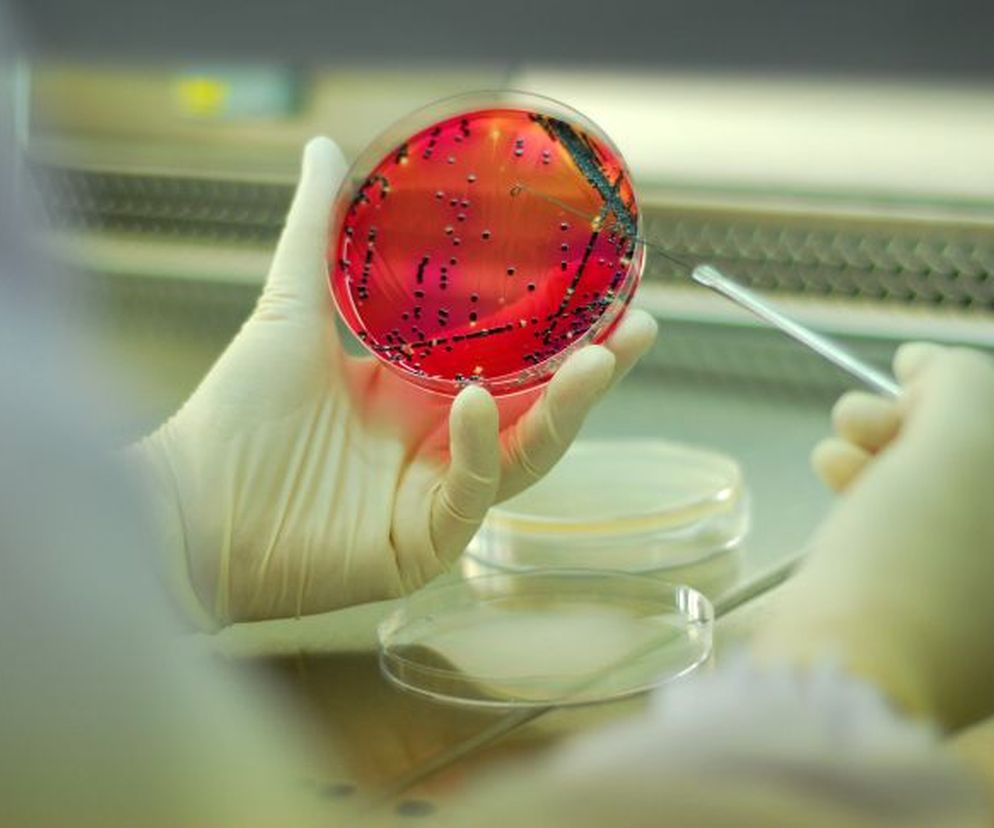

Choroby zakaźne to szerokie pojęcie, które obejmuje stany chorobowe wywołane przez czynniki chorobotwórcze i stanowiące zagrożenie dla zdrowia publicznego. W zależności od etiologii choroby czynnikiem powodującym przełamanie odporności organizmu mogą być grzyby, bakterie, wirusy lub toksyny. Do przeniesienia choroby zakaźnej najczęściej dochodzi w wyniku kontaktu z osobą chorą. Choroby zakaźne występują zarówno u osób dorosłych, jak i u dzieci.